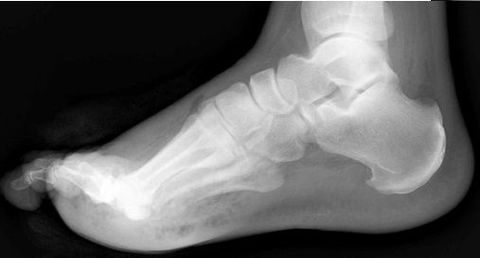

| What is this called? What does an anterior break indicate? What does a posterior break indicate? | Cyma Line/Midtarsal joint. Anterior break = pronated foot type Posterior break = supinated foot type |

| What is this? What foot type is this visible in? | Sinus tarsi/bullet hole sign. Pes cavo-varus |

| What is this? What foot type is this visible in? | Double talar dome sign. Pes cavo-varus |